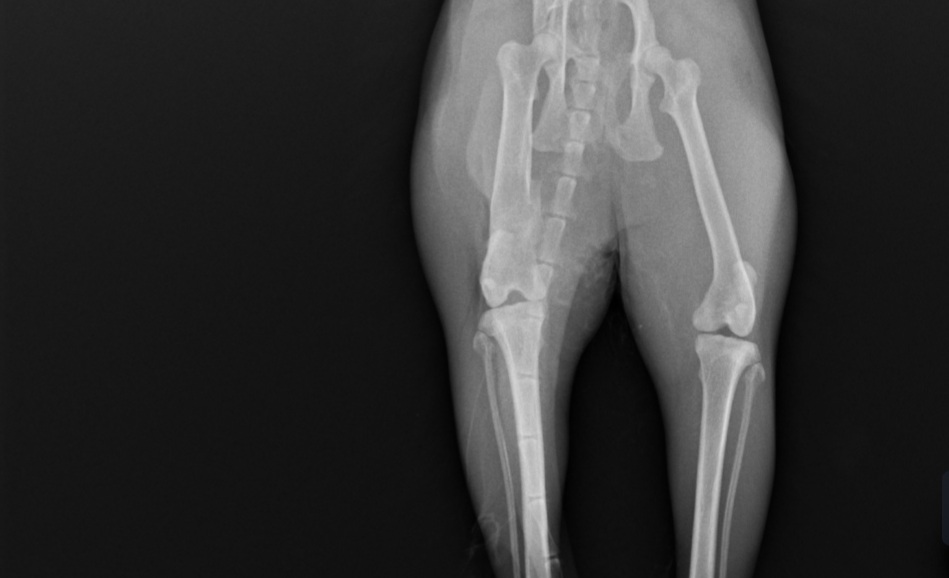

Trzy lata temu odłowiłam na osiedlu do sterylizacji dziką około 2letnią kotkę, która nazwaliśmy LUSI. Okazało się, że ma gorączkę, zapalenie płuc i inne przypadłości kota dziko - żyjącego. Z uwagi na konieczność leczenia, LUSIA zamieszkała z nami. Bardzo szybko zaadoptowała się do nowych warunków, więc została z nami. W tym roku zrealizowałam moje marzenie i przeprowadziłam się do mieszkania z ogródkiem. W trakcie prac wykończeniowych, przez nieuwagę pracownika wystraszona uciekła. Blisko 3 miesiące poszukiwałam ją bezskutecznie, aż do 18 marca Tego dnia szłam do domu i kotka słysząc mój głos, wyczołgała się z krzaków pod moje nogi ciągnąc za sobą tylną łapkę. Od razu udałam się do weterynarza i cios w serce... Okazało się, że LUSI została brutalnie, z wielką siłą potrącona przez samochód kilka tygodni wcześniej i pozostawiona w olbrzymim bólu i cierpieniu. Kotka po tym zdarzeniu zdziczała, ale nie dając za wygraną udałam się do znanego i polecanego specjalisty chirurga – ortopedy. Weterynarz zaleciła dalszą diagnostykę neurologiczną, leczenie farmakologiczne i dała nadzieję na wyzdrowienie kotki po zoperowaniu jej pękniętej miednicy i łapki. Niestety z uwagi na trudną sytuację finansową, nie jestem w stanie sama podołać tym kosztom. Bardzo proszę o wsparcie, abym mogła ulżyć kotce w cierpieniu.